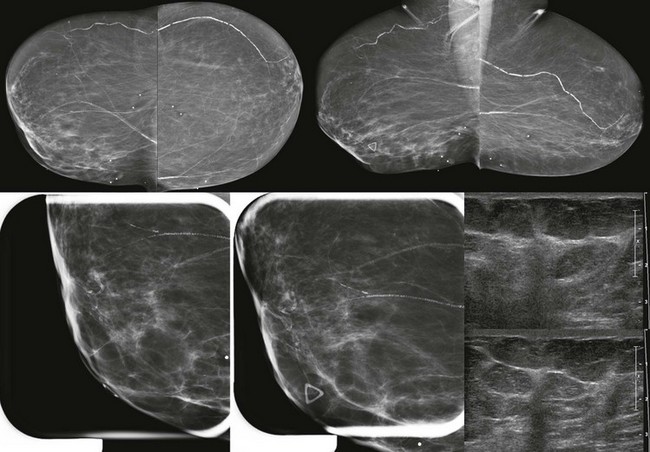

When the tumor is very large, the breast affected with ILC can appear to be getting smaller on mammography—the “shrinking breast” (Fig. 11-3). This is not due to the breast becoming physically smaller, but to the decreased compressibility of the breast tissue that is full of webs of cancer cells. If the contralateral breast compresses to a thickness of 5 cm, a breast with extensive ILC may only compress to 8 cm. Although this results in the appearance of a smaller breast on mammography, breast size is typically symmetric on clinical examination.

FIGURE 11-3 Shrinking Breast.

A 52-year-old woman noted thickening in her left breast. On clinical examination, the breasts are symmetric in size but the texture of the left breast is diffusely thickened. On mammography, the left breast appears to be smaller than the right. Biopsy showed ILC. Did you also notice the one-view asymmetry in the right medial breast? US of this area shows a small hypoechoic mass. Biopsy of the right breast showed IDC.